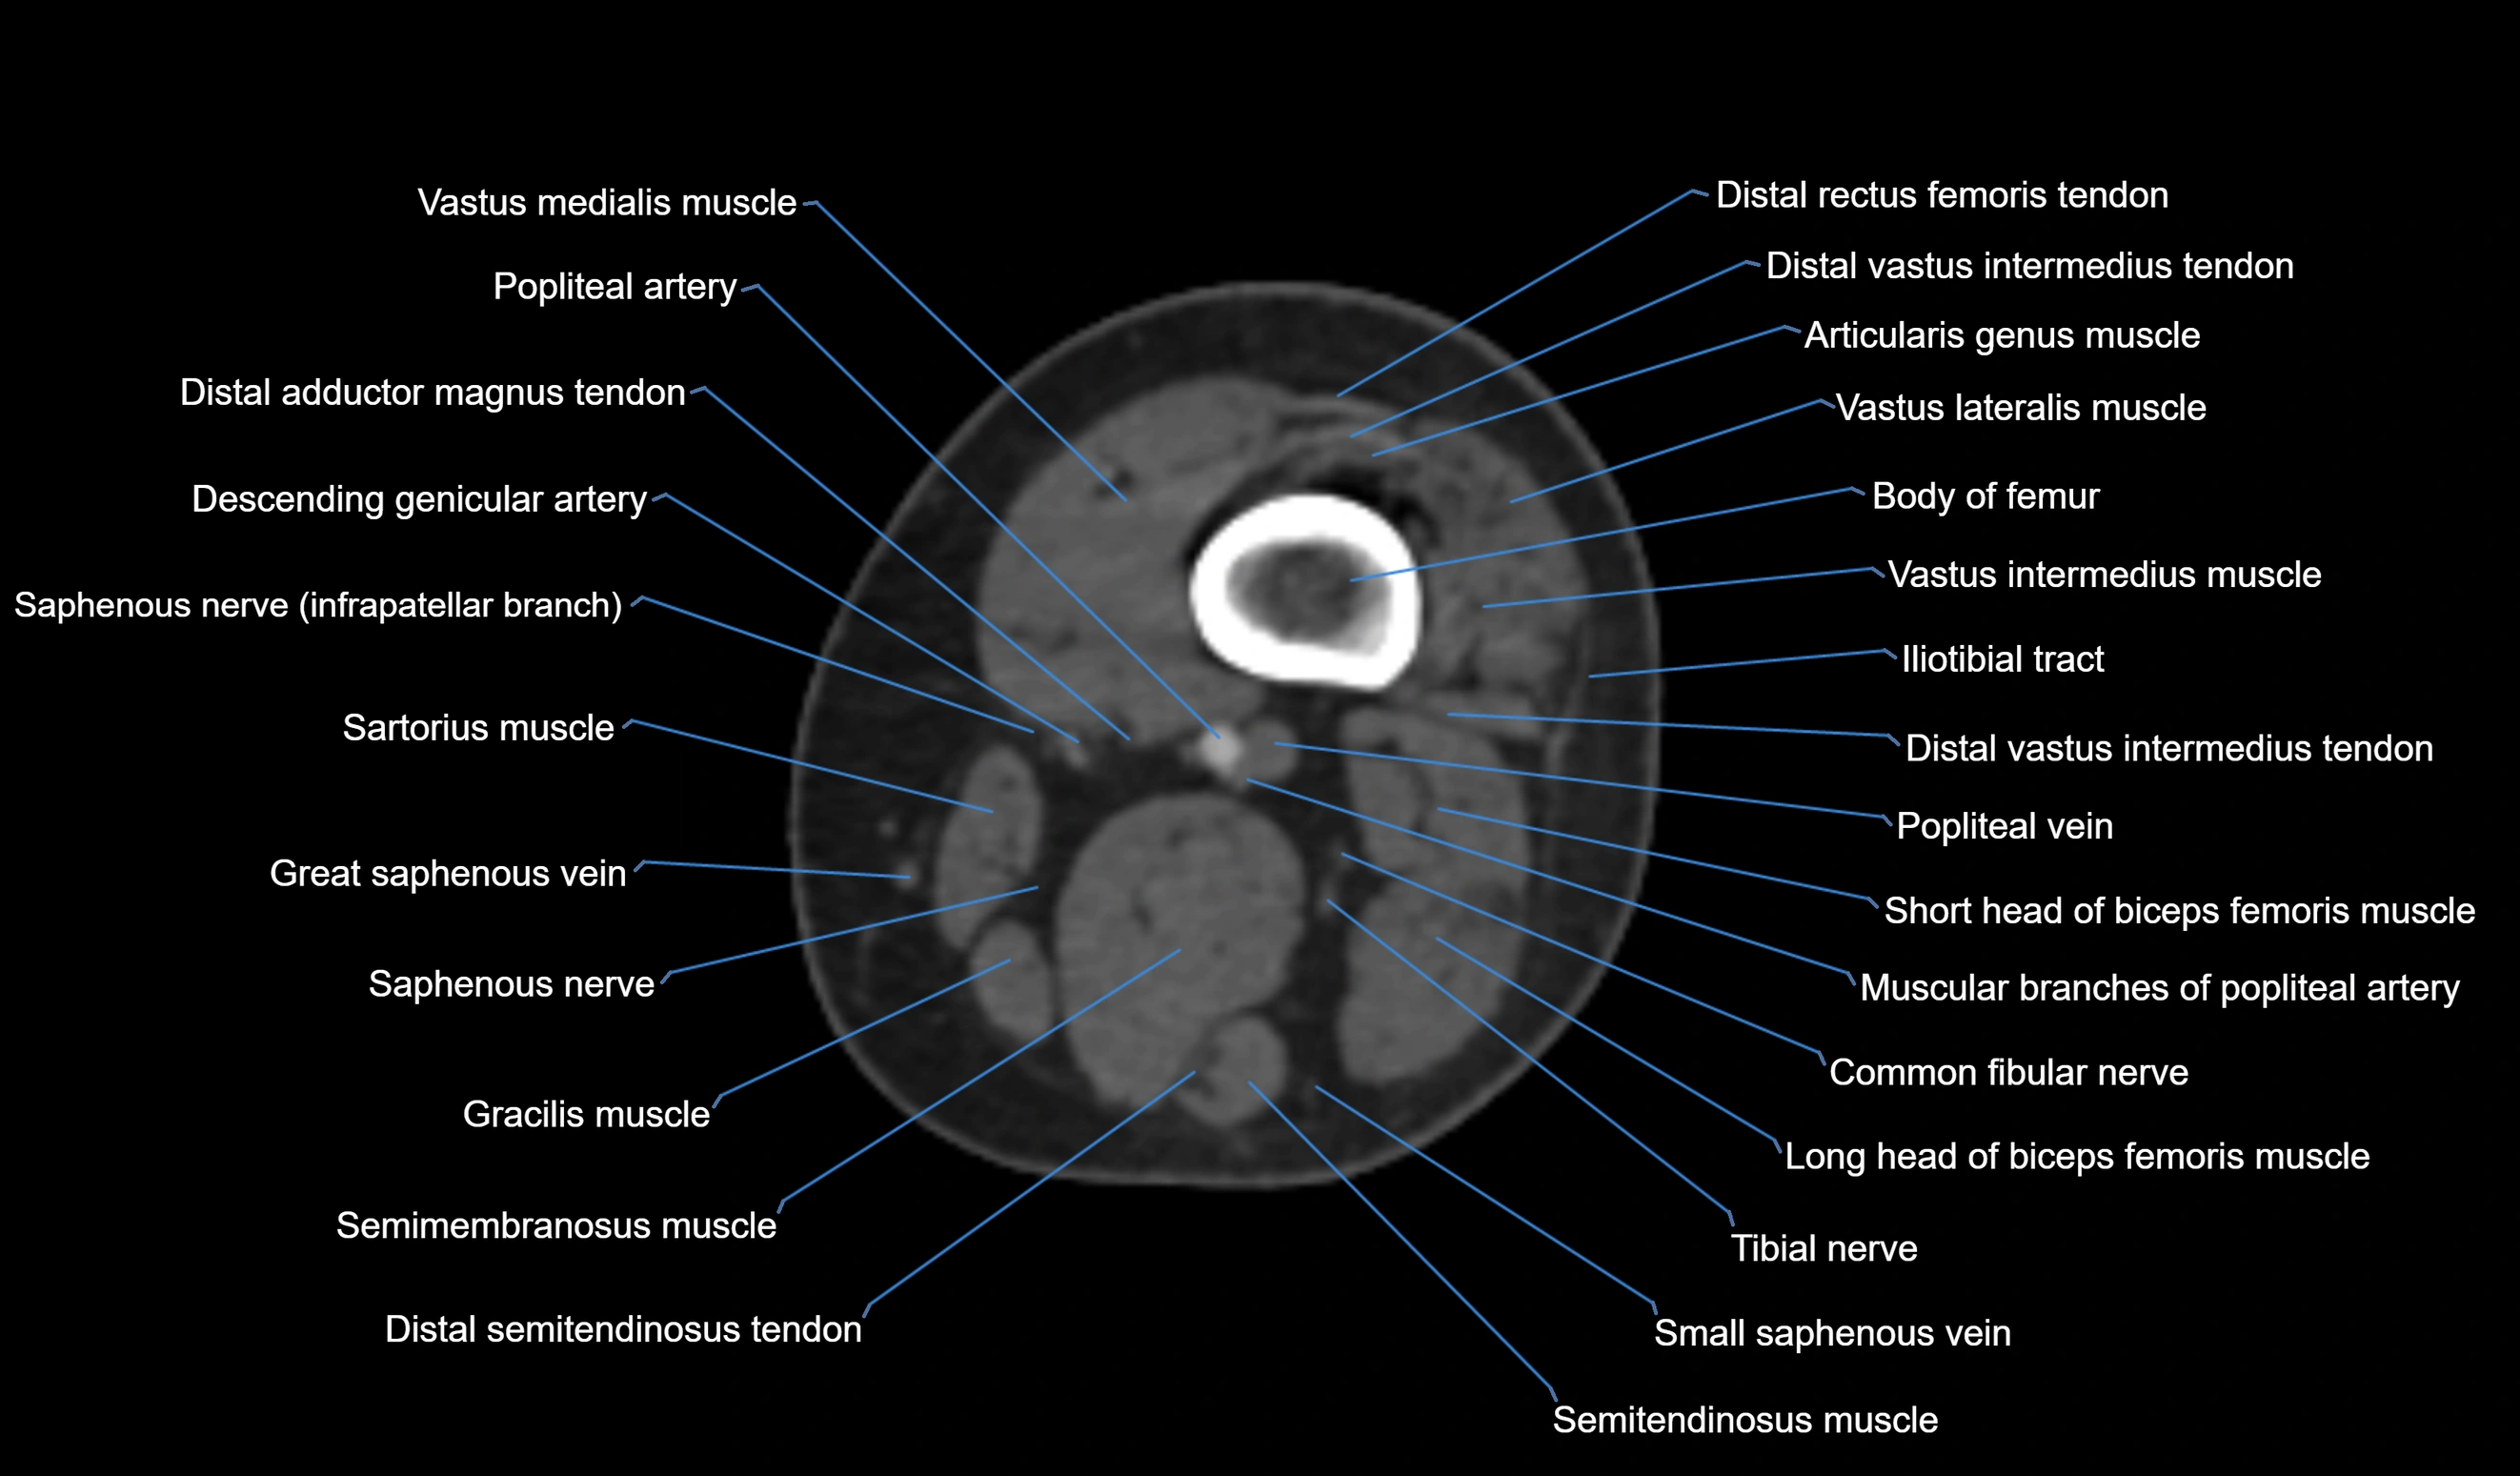

- Body of femur

- Common fibular nerve

- Descending genicular artery (Articular branches)

- Distal adductor magnus tendon

- Distal rectus femoris tendon

- Distal vastus intermedius tendon

- Popliteal artery

- Popliteal vein

- Saphenous nerve

- Sartorius muscle

- Semitendinosus muscle

- Tibial nerve

- Vastus lateralis muscle

- Vastus medialis muscle

- great saphenous vein